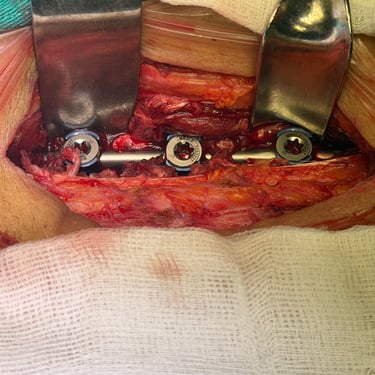

Fractura vertebral lumbar – Artrodesis con tornillos transpediculares (FTP).

La fractura vertebral lumbar es una lesión que puede comprometer la estabilidad de la columna y generar dolor, deformidad o déficit neurológico. En casos seleccionados, el tratamiento quirúrgico mediante artrodesis con tornillos transpediculares (FTP) permite una fijación firme de las vértebras afectadas, restaurando la alineación y brindando estabilidad inmediata. Esta técnica reduce el dolor, previene el desplazamiento vertebral y protege las estructuras neurológicas. La intervención oportuna, junto a una adecuada rehabilitación, favorece una recuperación funcional segura y mejora significativamente la calidad de vida del paciente.